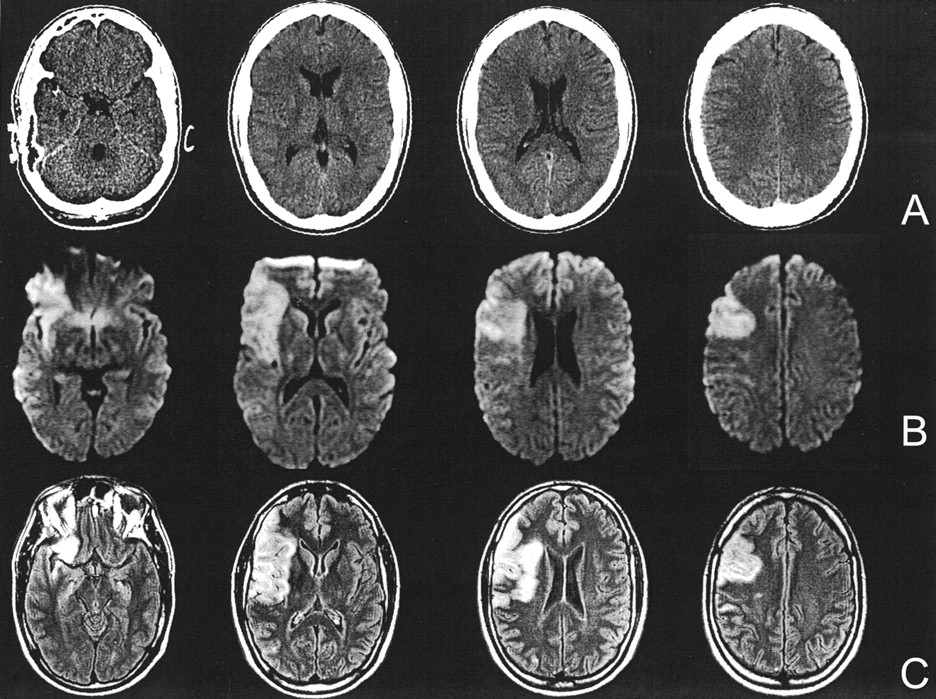

Case of a 35-year-old patient with left hemiparesis and neglect. (A) CT scans obtained 80 minutes after symptom onset, (B) DW images obtained 115 minutes after symptom onset, and (C) follow-up FLAIR images. Five of the six raters recognized parenchymal hypoattenuation of the right insular ribbon and frontotemporal regions on the CT scans. DW images and follow-up FLAIR images after 7 days illustrate a right MCA stroke caused by an MCA trunk occlusion.